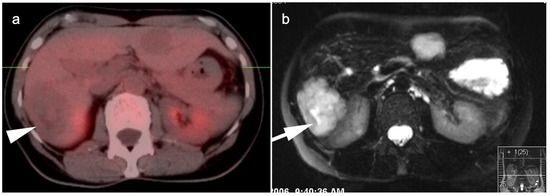

4. Hepatocellular Carcinoma